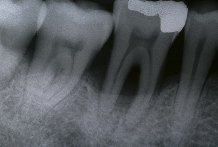

Las radiograf�as son necesarias para detectar, en caso de hayan ocurrido, lugares con p�rdida de hueso.